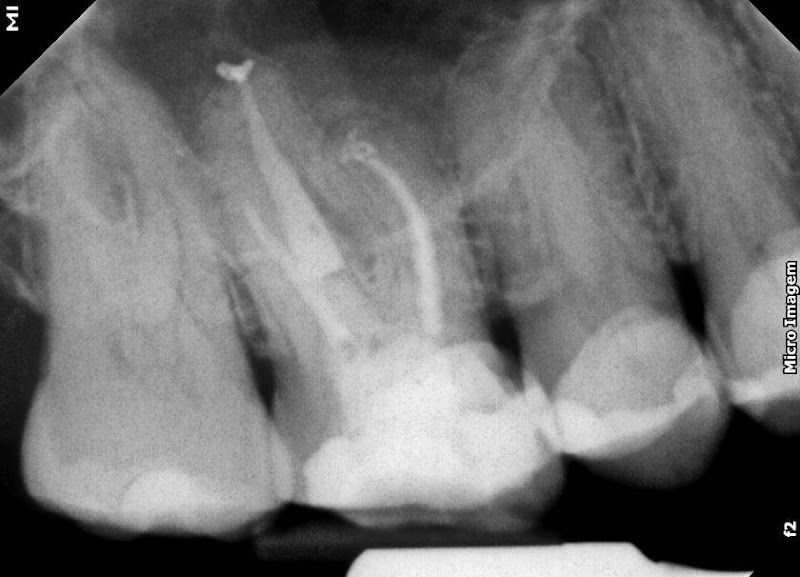

Fotos

+6 fotos